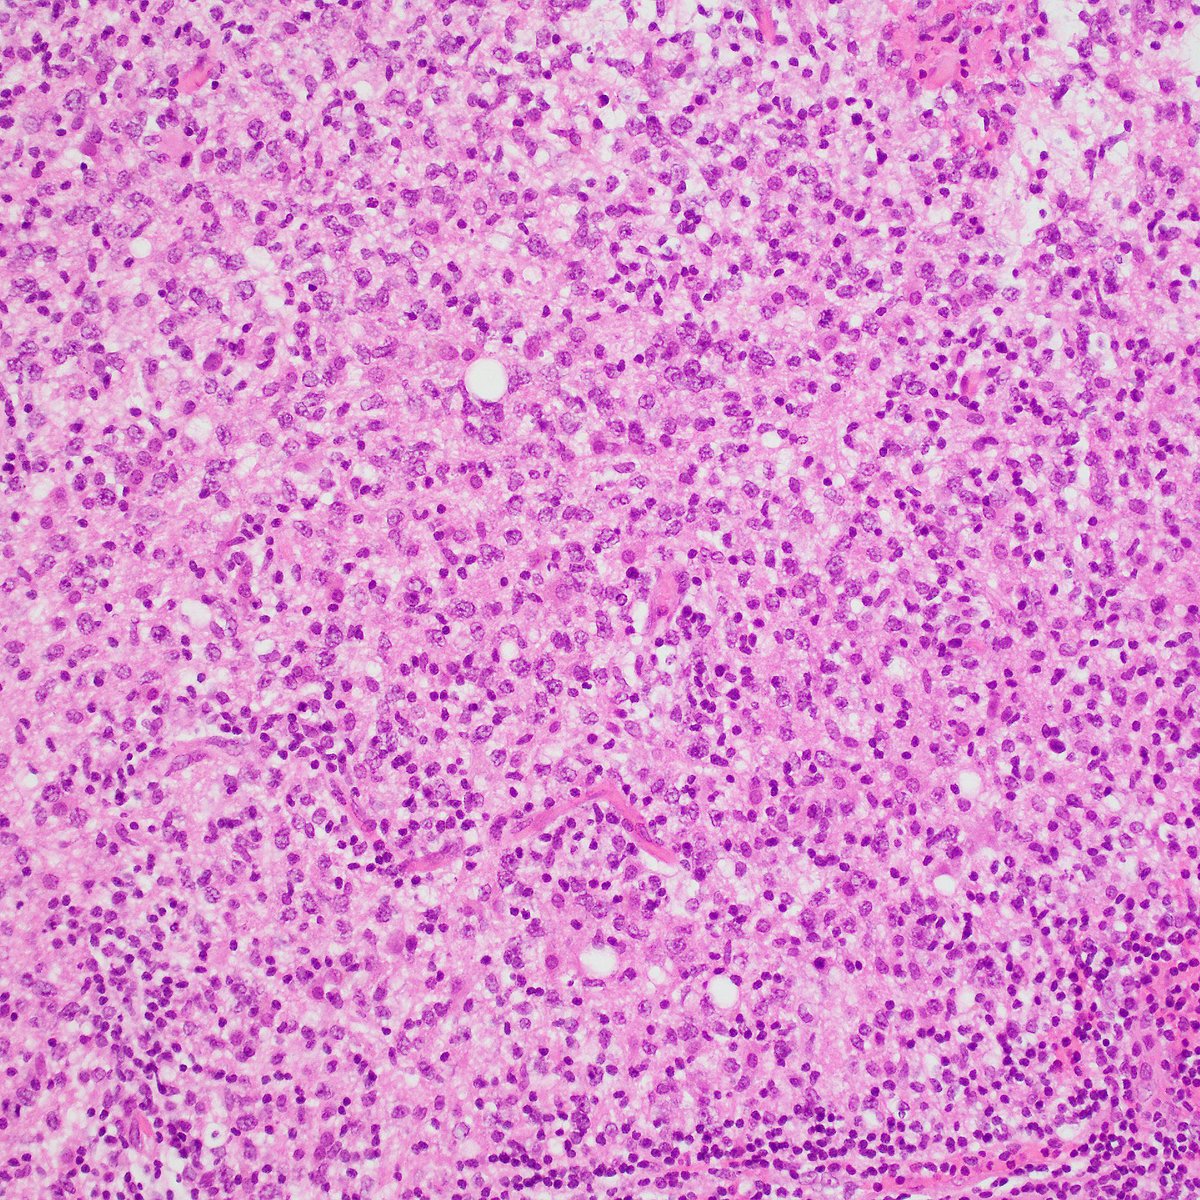

Adult patient with history of lymphoma, developed neurological symptoms and brain lesions. One of them was biopsied. The IHC is Ki-67. What do you think? Would you order any other stain(s)? #PathTwitter #Neuropath

A good clue is the presence of lymphoglandular bodies in the background. Smear prep is probably the best way to diagnose CNS lymphoma at frozen section. Here is the accompanying H&E permanent section and CD20. #PathTwitter #pathology #Neuropath #hemepath